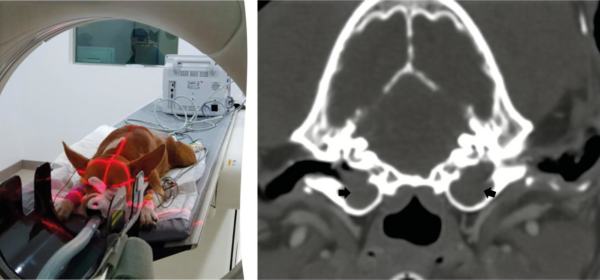

Tomografía computarizada (TC) y resonancia magnética (RMN)

La tomografía computarizada (TC) se considera la técnica de referencia para el estudio de las estructuras del oído medio. Permite valorar la integridad y el grosor del tímpano, la presencia de contenido líquido en oído medio, masas y alteraciones en la estructura ósea de la bulla y huesos adyacentes mediante la visualización de las estructuras anatómicas en sección transversal, evitando la superposición de estructuras característica de las radiografías.

El estudio de bullas timpánicas utiliza imágenes transversales contiguas de 1 a 3 mm, desde el área rostral a la bulla hasta el hueso temporal petroso. Se recomienda usar el campo de visión más pequeño posible y una técnica de alta densidad de mAs. El contraste yodado no suele administrarse, salvo sospecha de neoplasia u otitis interna. Las imágenes deben revisarse tanto en ventana ósea como de tejido blando.

En una posición adecuada en pacientes sin patología auricular ambas bullas se observan simétricas, permitiendo pequeñas variaciones anatómicas. El gas generalmente opaca la luz de la bulla timpánica y del conducto auditivo externo. La bulla timpánica presenta una pared delgada y delimitada. El conducto auditivo externo mantiene un grosor uniforme, sin evidencia de estrechamiento ni obstrucción luminal.

Los hallazgos tomográficos característicos de la otitis media comprenden el engrosamiento y la irregularidad de la pared de la bulla timpánica, la lisis ósea, presencia de material de densidad de tejido blando compatible con líquido o contenido tisular en su interior, así como signos asociados de otitis externa (imagen 8).